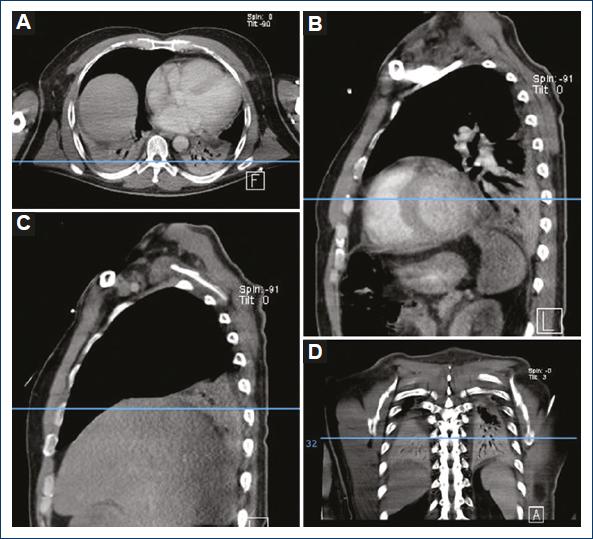

We evaluated 25 patients that we operated to drain the mediastinum for the diagnosis of mediastinitis, following the Estrera and Endo criteria, at the Hospital General de México “Dr. Eduardo Liceaga,” from August 1 2018 to July 31 2019. Ten (40%) were female patients and 15 (60%) were male patients. Twenty-one (84%) patients showed atelectasis and 4 (16%) did not have atelectasis. Of the patients that showed atelectasis, 17 (81%) were bilateral, 2 (9.5%) were right sided, and 2 (9.5%) were left sided. We also analyzed the occurrence of pleural effusion in this group. Fifteen (60%) patients had pleural effusion and 10 (40%) did not. Of the total patients with pleural effusion 11 (73.3%) were bilateral, 3 (20%) of the right side, and 1 (6.6%) of the left side (Figs. 1-3).

Figure 1 Patient with basal posterior segments atelectasis showing no pleural effusion. A: axial plane. B: sagittal plane left hemithorax. C: sagittal plane right hemithorax. D: coronal plane.